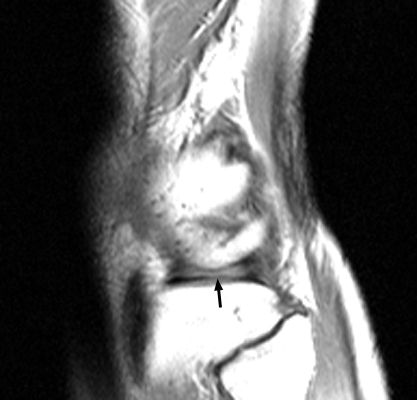

Absent Bow Tie Sign

Bucket-handle tear of the menisci

Multiple sagittal T1 weighted images which reveal loss of the normal bow-tie appearance of the meniscus. The "absent bow tie sign" is another good sign of a bucket handle tear of the meniscus. The absence of the normal bow-tie is secondary to the displaced fragment which makes up the "handle" of the bucket. Requirement for the absent bow tie sign mandates that the normal requirement of at least two adjacent sagittal images with a normal meniscal body segment appearance is not present.

bulletHelms CA, Laorr A, Cannon WD Jr: The absent bow tie sign in bucket-handle tears of the menisci in the knee. AJR Am J Roentgenol 1998 Jan;170(1):57-61.          [See related articles]